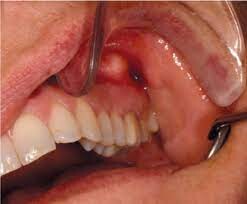

Apical periodontitis refers to the inflammation of the periodontium — the tissue that surrounds your teeth. Apical means "relating to the apex," so inflammation usually occurs around the tip — or apex — of the tooth's root. Two types of apical periodontitis exist:

Typically, apical periodontitis occurs when there's another problem with the tooth. For example, inflammation can develop if a person has an untreated cavity. In some cases, apical periodontitis can develop if the pulp of the tooth becomes infected or dies. Injury or trauma to the tooth can also lead to apical periodontitis.

Apicoectomy. If the infection develops or continues after the root canal, you might require an apicoectomy. During this procedure, the endodontist removes the tip of the tooth's root and infected tissue, then seals the end of the root with a filling.